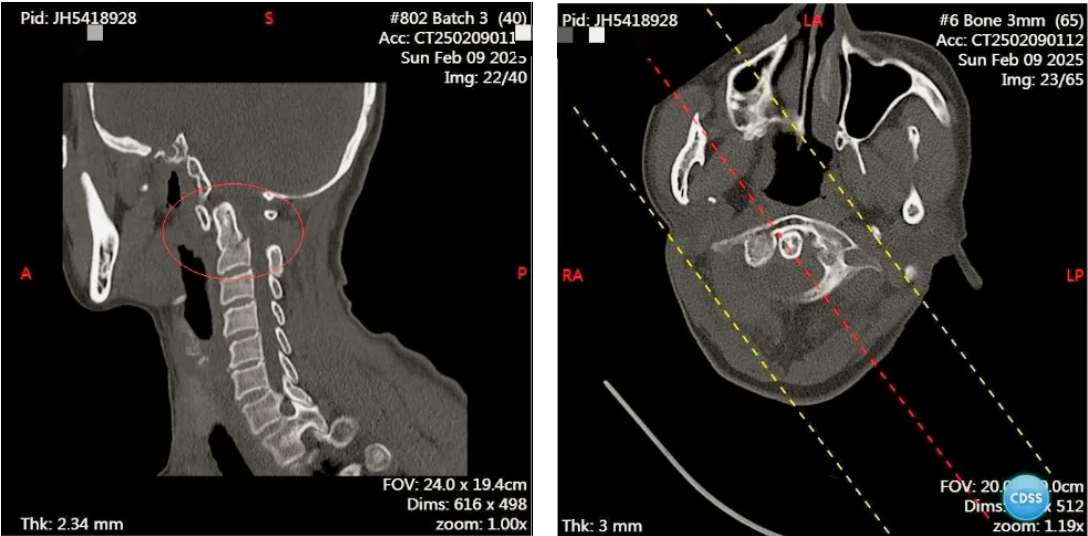

患者刘女士因不慎受伤后导致颈部剧痛,活动严重受限,紧急送往我院后,经颈椎 CT 检查,确诊为枢椎齿状突骨折。

李涛副院长接诊后,细致询问病史、查体并阅片,深入分析病情。他指出,需立即为患者进行枕颌带牵引复位,并完善检查,计划一周后实施微创颈椎前路枢椎骨折闭合复位空心螺钉内固定术,以固定骨折齿状突,帮助患者早期活动。

李涛副院长在术中应用椎间孔镜准确定位进钉点,精准地将空心螺钉植入,成功实现骨折复位固定。整个手术过程几乎没有出血,每一个动作都精准无误。

术后复查显示,齿状突骨折完美复位,螺钉位置精准。